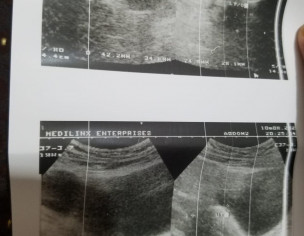

Asking for Self, Female, 21 years old, Karachi

Mere right ovary mein cyst aya hy measuring 4.2*3.4,,plz ye btaden kia ye medicenes se thk hojaegi??

Attach Photo here: